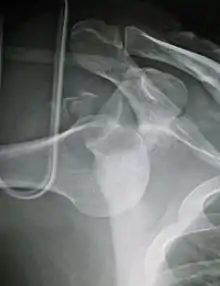

| Anterior dislocation of the left shoulder. | |

In over 95% of shoulder dislocations, the humerus is displaced anteriorly.[7] In most of those, the head of the humerus comes to rest under the coracoid process, referred to as sub-coracoid dislocation. Sub-glenoid, subclavicular, and, very rarely, intrathoracic or retroperitoneal dislocations may also occur.[8]

Anterior dislocations are usually caused by a direct blow to, or fall on, an outstretched arm. The person typically holds his/her arm externally rotated and slightly abducted.